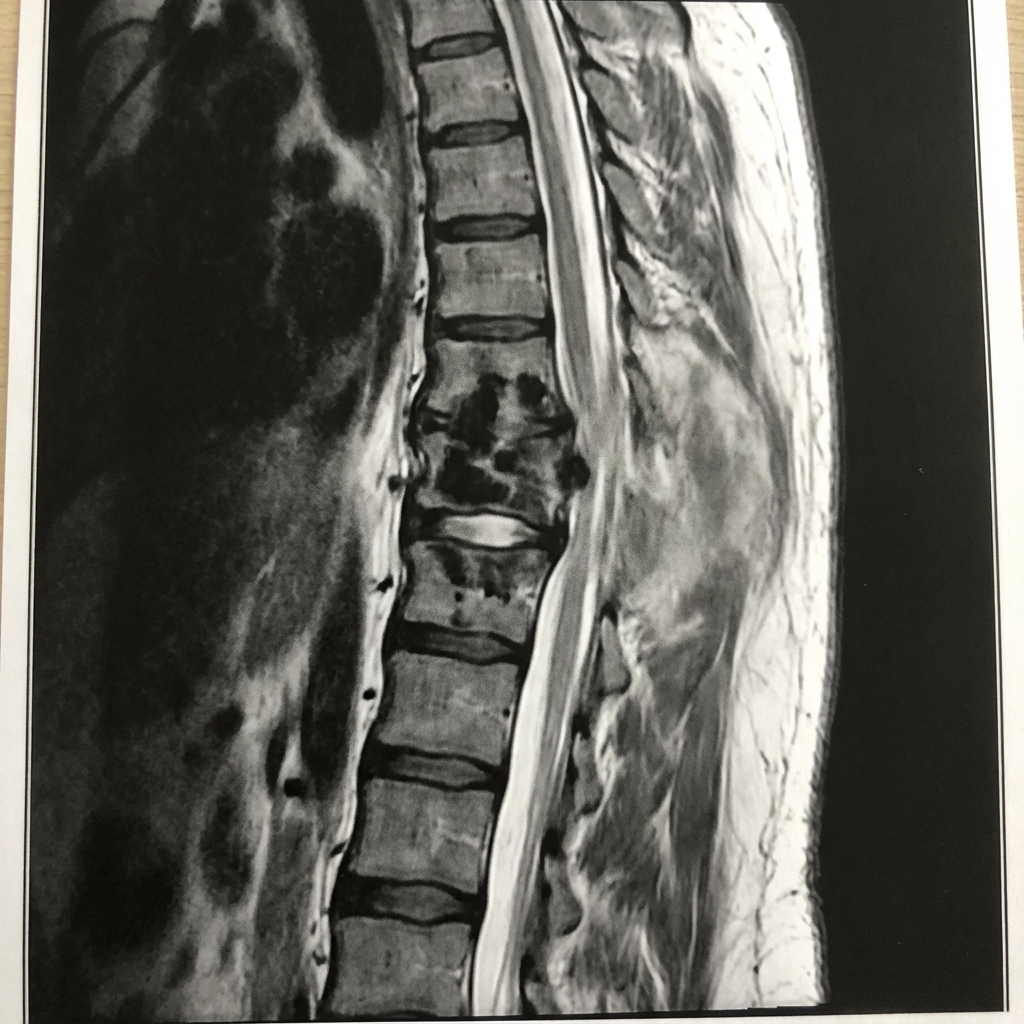

Sagittal and axial T2-weighted MRI demonstrating destruction of T10 and T11 vertebral bodies with relative preservation of the disc spaces (characteristic). Large paravertebral abscess extends anterolaterally. There is gibbus kyphotic deformity and spinal cord compression. This represents spinal tuberculosis (Pott's disease) requiring antitubercular chemotherapy and surgical consideration.

Describe the MRI findings and how do they differ from pyogenic infection?